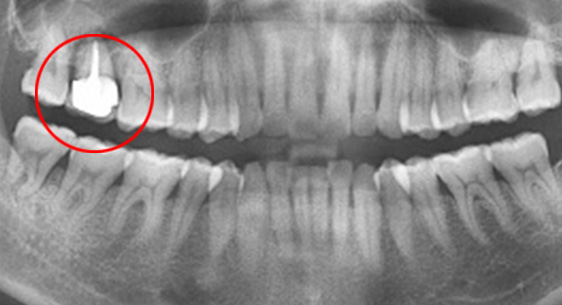

심한 염증으로 치조골이 광범위하게 소실, 아래쪽 신경관이 가까이 있어 치근단수술이 불가능한 상태, 타 병원에서 임플란트 진단을 받았지만,

고운미소치과에서 치아를 발치하고 뿌리 쪽 염증을 제거한 후 발치한 치아를 다시 심는 치아재식술을 시행하였습니다.

기존 신경치료 부위에 염증과 치조골이 소실되고 있는 상태

치아를 발치하고 염증을 제거, MTA로 충전하고 치아를 다시 심음. (난이도 최상)